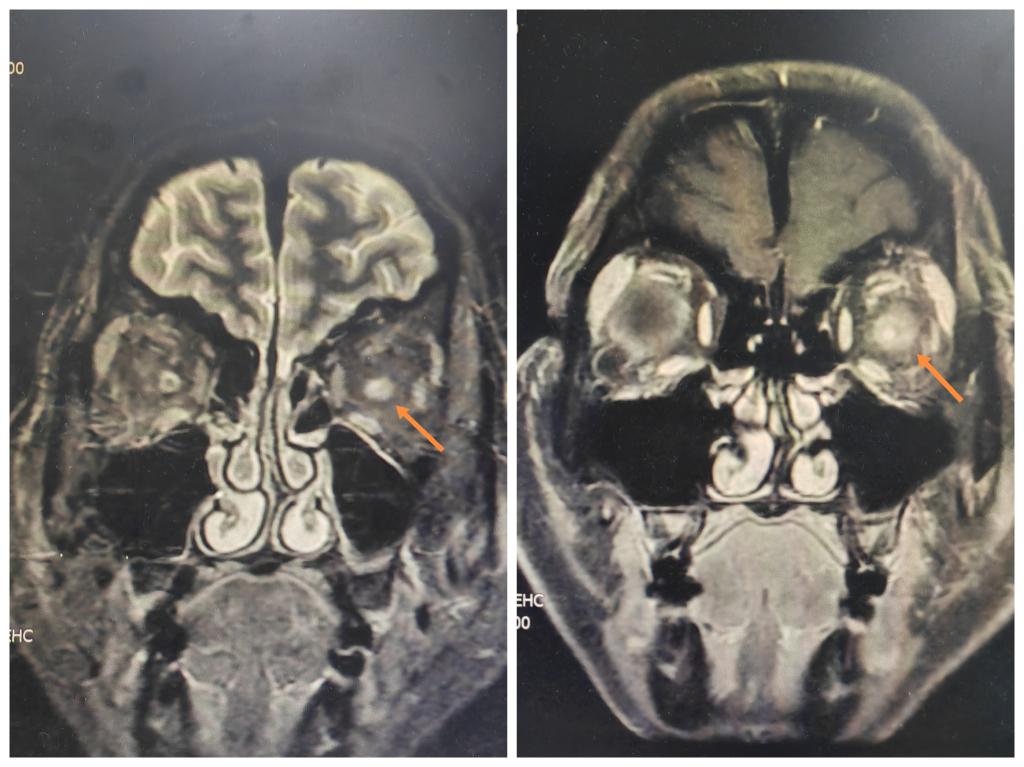

入院后王建明教授、范雅稚副主任、邢瑶主治医师为患者制定了详细完善的诊疗方案,各项眼科检查、眼眶MRI、全身检查均快速进行,争取在短时间内明确诊断,为患者的治疗争取宝贵的治疗时间。入院第三天,患者左眼视力仍持续下降,左眼仅存光感。团队的每一位医师与患者一样心急如焚。此时,患者头颅及眼眶MRI结果提示:眼眶MRI提示左眼视神经肿胀增粗,T2高信号伴T1强化明显。血清中枢脱髓鞘抗体提示:抗AQP4抗体阳性,结合各项眼科检查结果,明确诊断:左眼视神经脊髓炎相关性视神经炎(抗AQP4抗体阳性)。排除糖皮质激素使用禁忌后,王建明教授团队为患者制定了甲泼尼龙静点1 g/d后剂量阶梯减半的激素序贯治疗方案,并联合营养神经、改善循环药物治疗。然而7天后,患者左眼视力仍为手动/眼前。由于患者对糖皮质激素治疗反应差,充分与患者沟通后决定联合血浆置换治疗。请肾病内科及输血科会诊后,得到两个科室大力支持。血浆置换过程中,肾病科、输血科为患者提供了专业的技术支持,克服了血浆制品缺乏等各种困难。眼科护理团队积极配合,全方位监护,每次置换结束后复查各项指标进行安全性评估。通过三个科室的通力配合,患者完成了双重血浆置换,隔日一次,共四次。第四次置换结束后,左眼裸眼视力0.02。出院后,患者左眼视力持续恢复,眼痛及头痛症状明显改善,视野缺损范围较前显著缩小,复查血常规、肝肾功电解质、凝血功能无明显异常,眼科门诊密切随访。